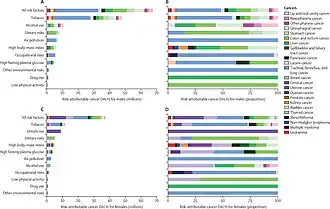

About 33% of deaths from cancer are caused by tobacco and alcohol consumption, obesity, lack of fruit and vegetables in diet and lack of exercise.[2][9][10] Other factors include certain infections, exposure to ionizing radiation, and environmental pollutants.[3] Infection with specific viruses, bacteria and parasites is an environmental factor causing approximately 16–18% of cancers worldwide.[11] These infectious agents include Helicobacter pylori, hepatitis B, hepatitis C, HPV, Epstein–Barr virus, Human T-lymphotropic virus 1, Kaposi's sarcoma-associated herpesvirus and Merkel cell polyomavirus. Human immunodeficiency virus (HIV) does not directly cause cancer but it causes immune deficiency that can magnify the risk due to other infections, sometimes up to several thousandfold (in the case of Kaposi's sarcoma). Importantly, vaccination against the hepatitis B virus and the human papillomavirus have been shown to nearly eliminate the risk of cancers caused by these viruses in persons successfully vaccinated prior to infection.

The majority of cancers, some 90–95% of cases, are due to genetic mutations from environmental and lifestyle factors.[3] The remaining 5–10% are due to inherited genetics.[3] Environmental refers to any cause that is not inherited, such as lifestyle, economic, and behavioral factors and not merely pollution.[44] Common environmental factors that contribute to cancer death include tobacco use (25–30%), diet and obesity (30–35%), infections (15–20%), radiation (both ionizing and non-ionizing, up to 10%), lack of physical activity, and pollution.[3][45] Psychological stress does not appear to be a risk factor for the onset of cancer,[46][47] though it may worsen outcomes in those who already have cancer.[46]

Alcohol increases the risk of cancer of the breast (in women), throat, liver, oesophagus, mouth, larynx, and colon.[58] In Western Europe, 10% of cancers in males and 3% of cancers in females are attributed to alcohol exposure, especially liver and digestive tract cancers.[59] Cancer from work-related substance exposures may cause between 2 and 20% of cases,[60] causing at least 200,000 deaths.[61] Cancers such as lung cancer and mesothelioma can come from inhaling tobacco smoke or asbestos fibers, or leukemia from exposure to benzene.[61]

Greater than 30% of cancer deaths could be prevented by avoiding risk factors including: tobacco, excess weight/obesity, poor diet, physical inactivity, alcohol, sexually transmitted infections and air pollution.[135] Further, poverty could be considered as an indirect risk factor in human cancers.[136] Not all environmental causes are controllable, such as naturally occurring background radiation and cancers caused through hereditary genetic disorders and thus are not preventable via personal behavior.

In 2019, ~44% of all cancer deaths – or ~4.5 M deaths or ~105 million lost disability-adjusted life years – were due to known clearly preventable risk factors, led by smoking, alcohol use and high BMI, according to a GBD systematic analysis.[131]